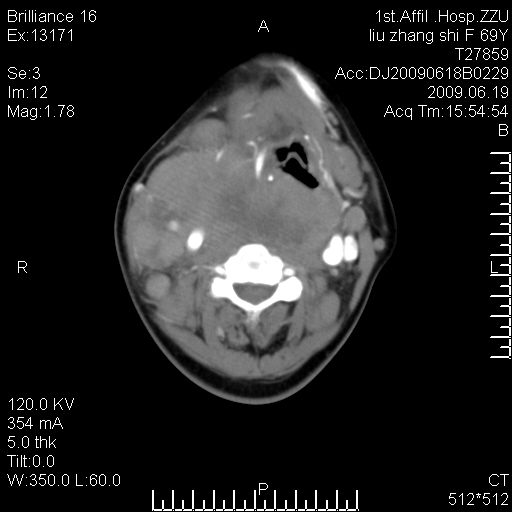

标题: CT26782:女,69岁,颈部占位,3天后公布病理结果。

【病理证实系列】女,69岁,颈部占位,有病理结果,3天后公布。(由于病例时间较久,临床资料不全,请网友见谅)本系列将有几百种常见、少见及罕见病例,均经病理证实。病例资料来自郑州大学第一附属医院。与网友共享,本人有空就发。

甲状腺癌并颈部淋巴结转移。感谢楼主的良苦用心,谢谢。

甲状腺癌并颈部淋巴结转移。

需与鼻咽癌鉴别!

支持甲状腺癌广泛侵及周围结构并颈部淋巴结转移。

鉴别:淋巴瘤、恶性神经源性病变、恶性纤维组织细胞瘤。

病理结果:颈部非霍奇金淋巴瘤。